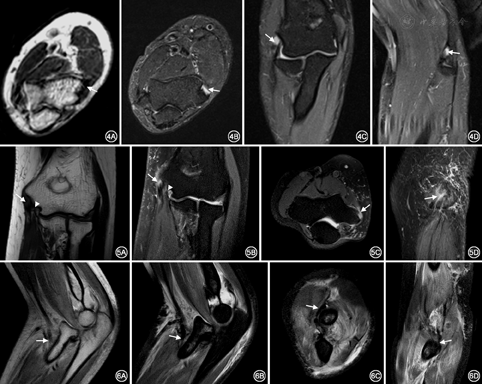

20例(40侧)正常志愿者的肘关节肌腱结构在MR各序列上均表现为细线样或条带状低信号,肌纤维走行连续(图2)。屈肌总腱、伸肌总腱在冠状位显示最佳;肱肌肌腱、肱二头肌腱在轴位和矢状位显示最佳,肱三头肌腱在矢状位和轴位显示最佳。伸肌总腱起于肱骨外上髁,MR表现为均匀细线样低信号(图2A)。屈肌总腱起源于肱骨内上髁,MR表现为均匀条状低信号(图2B),其深层线样低信号为内侧副韧带前束,起于肱骨内上髁前下部,止于尺骨冠突内侧。肱二头肌腱远端表现为条带状低信号,穿过肘窝附着于桡骨粗隆(图2C,图2D,图2E,图2F和图3),其远端无腱鞘,但有滑囊(桡侧囊)与桡骨粗隆紧密结合。肱肌肌腱远端,表现为条带状低信号,远端插入尺骨近端骨皮质(2C~2F)。肱三头肌腱远端结构分三层,长头和外侧头肌纤维在远端构成联合腱插入尺骨鹰嘴,表现为纤维结构连续的带状低信号(2E、2F),内侧头肌腱很短插入鹰嘴前方。

38例肘关节外伤患者,44条肌腱损伤,其中伸肌总腱损伤14例(6例伴桡侧副韧带损伤,2例伴肘关节骨折及桡侧副韧带损伤,1例伴肘关节脱位、尺侧副韧带及外侧副韧带复合体损伤,1例伴尺侧副韧带损伤),MR表现为伸肌总腱肱骨外上髁附着处部分纤维走形不连续性,PD-FS序列信号增高,局部被液体充填(图4)。屈肌总腱损伤10例(1例伴肘关节脱位、尺侧副韧带及外侧副韧带复合体损伤,3例伴尺侧副韧带损伤,1例伴肘关节脱位及环状韧带损伤),MR表现为纤维走形连续性不佳,T1WI序列呈低信号,PD-FS序列呈高信号,其周围软组织水肿(图5)。肱二头肌腱损伤3例(2例伴肘关节脱位、尺侧副韧带及外侧副韧带复合体损伤),MR表现为肱二头肌腱远端迂曲增粗,部分纤维不连续,桡骨粗隆附着点处T1WI序列呈低信号,PD-FS序列呈高信号改变,伴桡骨头脱位,骨髓及周围软组织水肿,关节腔积液(图6)。肱肌肌腱损伤7例(1例伴尺侧副韧带损伤,1例伴肘关节骨折,伴肘关节脱位及环状韧带损伤1例),MRI表现为肱肌腱尺骨粗隆附着端迂曲,T1WI序列呈水样低信号,PD-FS序列腱鞘走行区内信号增高,腱鞘积液(图7)。肱三头肌腱损伤10例(其中1例伴有骨折),MR表现为肱三头肌腱远端长头和外侧头部分撕裂,表现为迂曲增粗,鹰嘴附着端部分纤维不连续,T1WI序列纤维增粗,形态不规则,呈低信号改变,PD-FS序列肌纤维迂曲增粗,其内可见条状高信号改变,为纤维部分撕裂被液体充填所致(图8)。